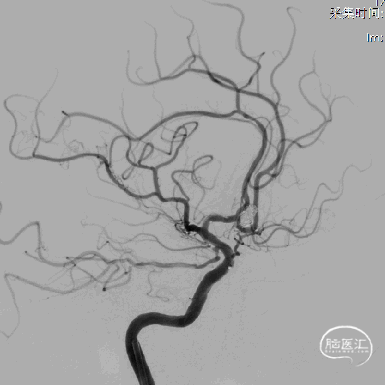

13、支架置入后左侧大脑前动脉血流好转。

14、栓塞后造影。

栓塞后正位造影